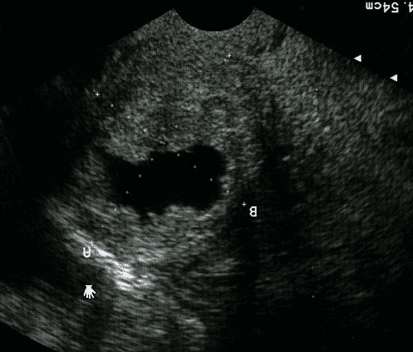

U xơ cơ tử cung dưới niêm mạc lâm sàng thường gây rong kinh, rong huyết